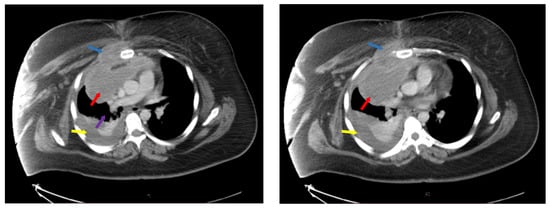

Disease extension was evaluated with neck, chest, abdomen and pelvis computer tomography (CT) as seen in Figure 1., which revealed multiple retroclavicular adenopathies, with compression of right subclavian vein, bilateral axillary and cervical adenopathies of up to 19 mm and an anterior mediastinal adenopathy block of 110/85 mm, with invasion of anterior thoracic wall and right pectoris muscle, inclusion and compression of thoracic aorta and superior vena cava. There was a right pleural effusion of 25 mm and pericardial effusion of 10 mm.

Figure 1. Computer tomography at diagnosis showing mediastinal adenopathy block (red arrows), with compression of vasculature (purple arrow) and invasion of thoracic wall and right pectoral muscle (blue arrows), pleural effusion (yellow arrows). Left side—ce reprezinta (descriere), Right side—ce reprezinta (descriere).